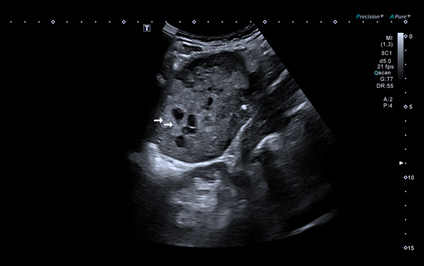

Se completa la exploración en la consulta de Atención Primaria, con ecografía a pie de cama donde se visualiza una imagen de ecoestructura heterogénea, con zonas hiperecoicas y zonas anecoicas, yuxtarrenal izquierda y que capta Doppler en algunas zonas.